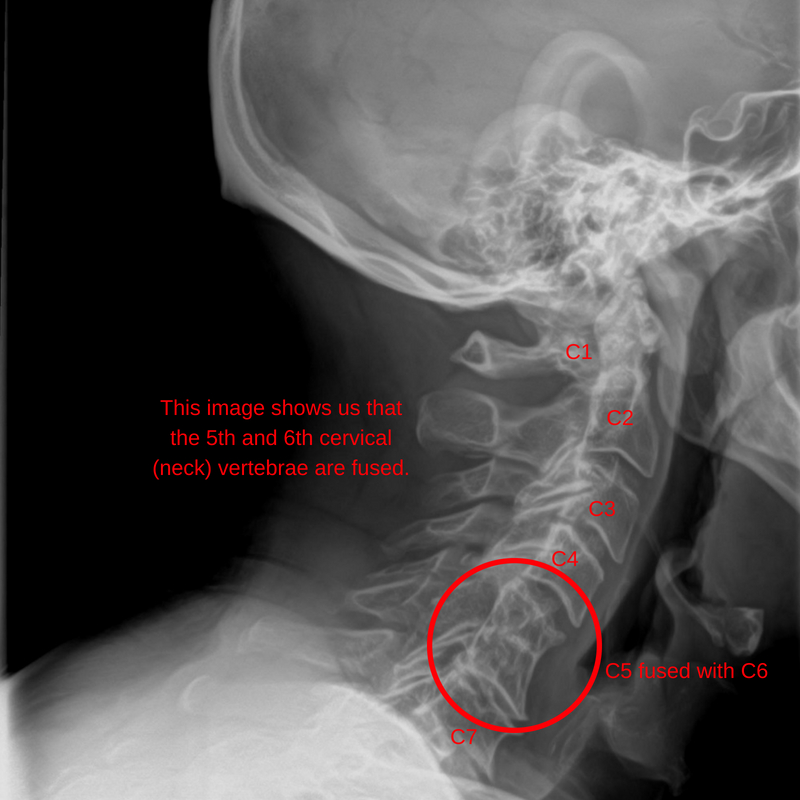

During the initial consolation and chiropractic exam Colin* displayed restricted movement in his neck and had minimal movement throughout the lower neck joints.

Again, after his thorough health history and physical exam, we had clinical reasoning to take X-rays and proceeded with a full spine series. These X-rays show a congenital anomaly in his lower neck called a ‘Block Vertebrae’. What this means is that when Colin’s spine formed, some of the vertebrae in his neck had developed abnormally, two of his vertebra had formed together as one.

Now although this does not have any implications for Colin in terms of needing any other treatment, it does have a big effect on how we adjust his cervical spine (neck).

Again, this is something that would have been impossible to identify without the X-ray, all it felt like was restricted motion. The use of X-ray, in this case, has allowed us to create a more specific chiropractic care plan for him that will cater to his individual body and will help him progress better.